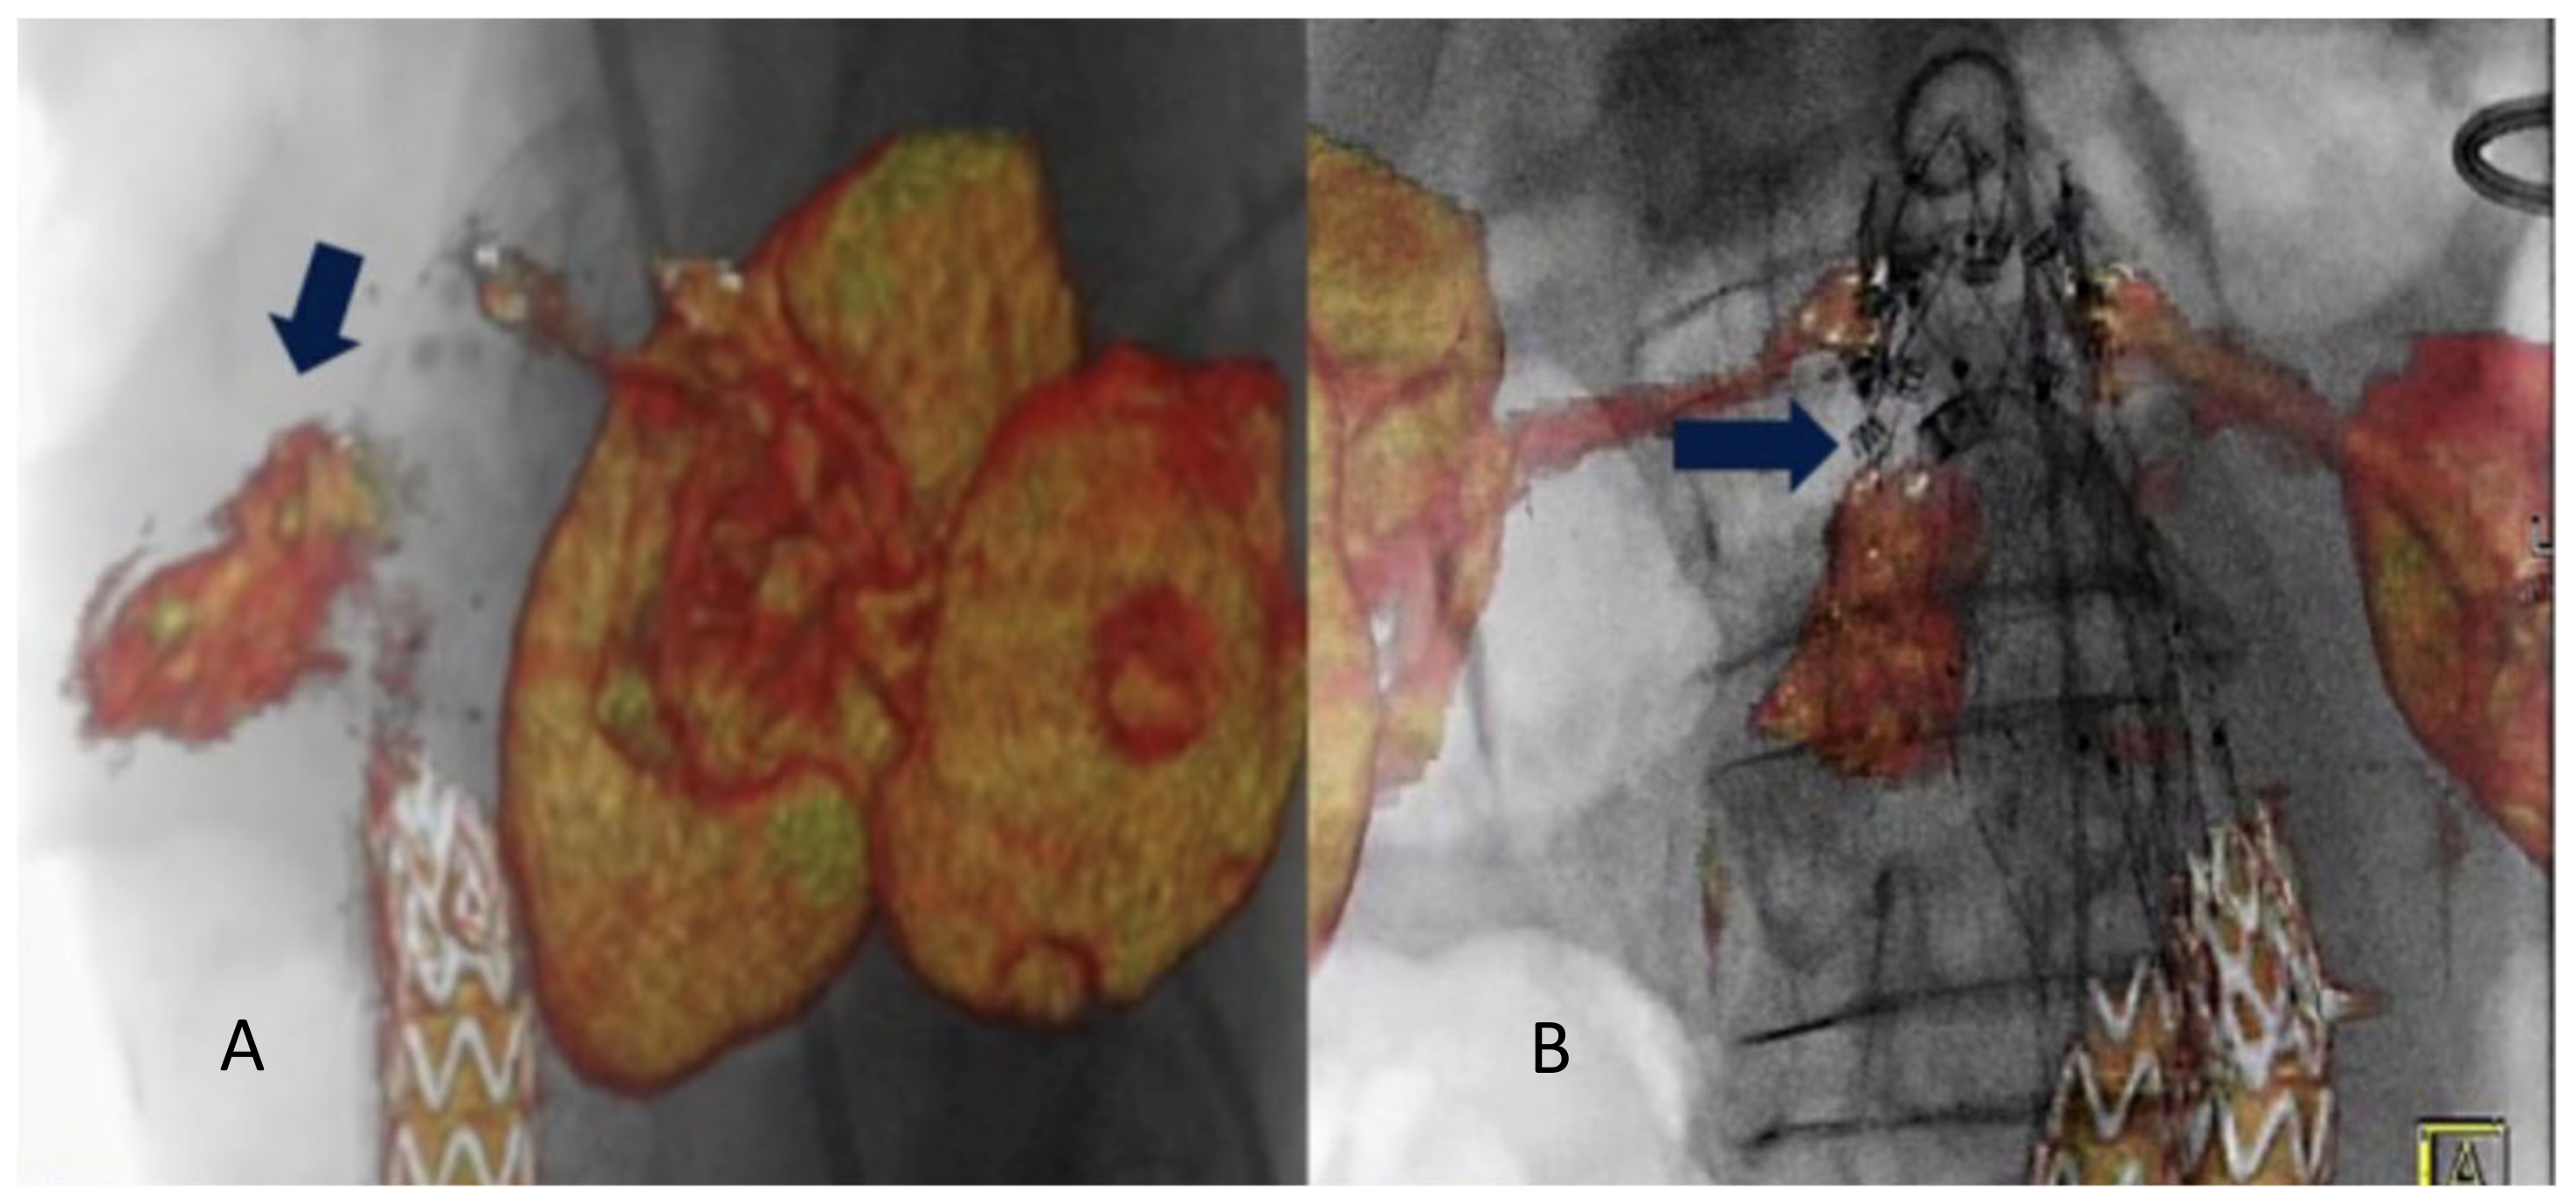

- Tinelli, G.; De Nigris, F.; Flore, R.; Santoliquido, A.; Tshomba, Y. Endoanchors under 3D image fusion for a type IA endoleak after EVAR. Clin. Case Rep. 2019, 7, 529–532. [Google Scholar] [CrossRef]